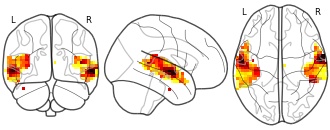

Atlases of cognition with large-scale human brain mapping: human sound

EmailClick to copy linkLink copied Cite(2018). Atlases of cognition with large-scale human brain mapping: human sound [Dataset]. http://identifiers.org/neurovault.image:109669niftiAvailable download formatsUnique identifierhttps://identifiers.org/neurovault.image:109669Dataset updatedDec 3, 2018License

Cite(2018). Atlases of cognition with large-scale human brain mapping: human sound [Dataset]. http://identifiers.org/neurovault.image:109669niftiAvailable download formatsUnique identifierhttps://identifiers.org/neurovault.image:109669Dataset updatedDec 3, 2018LicenseCC0 1.0 Universal Public Domain Dedicationhttps://creativecommons.org/publicdomain/zero/1.0/

License information was derived automaticallyDescriptionhuman_sound.nii.gz

Collection description

Atlases of various aspects of cognition estimated via large-scale decoding across many studies

Subject species

homo sapiens

Map type

Other